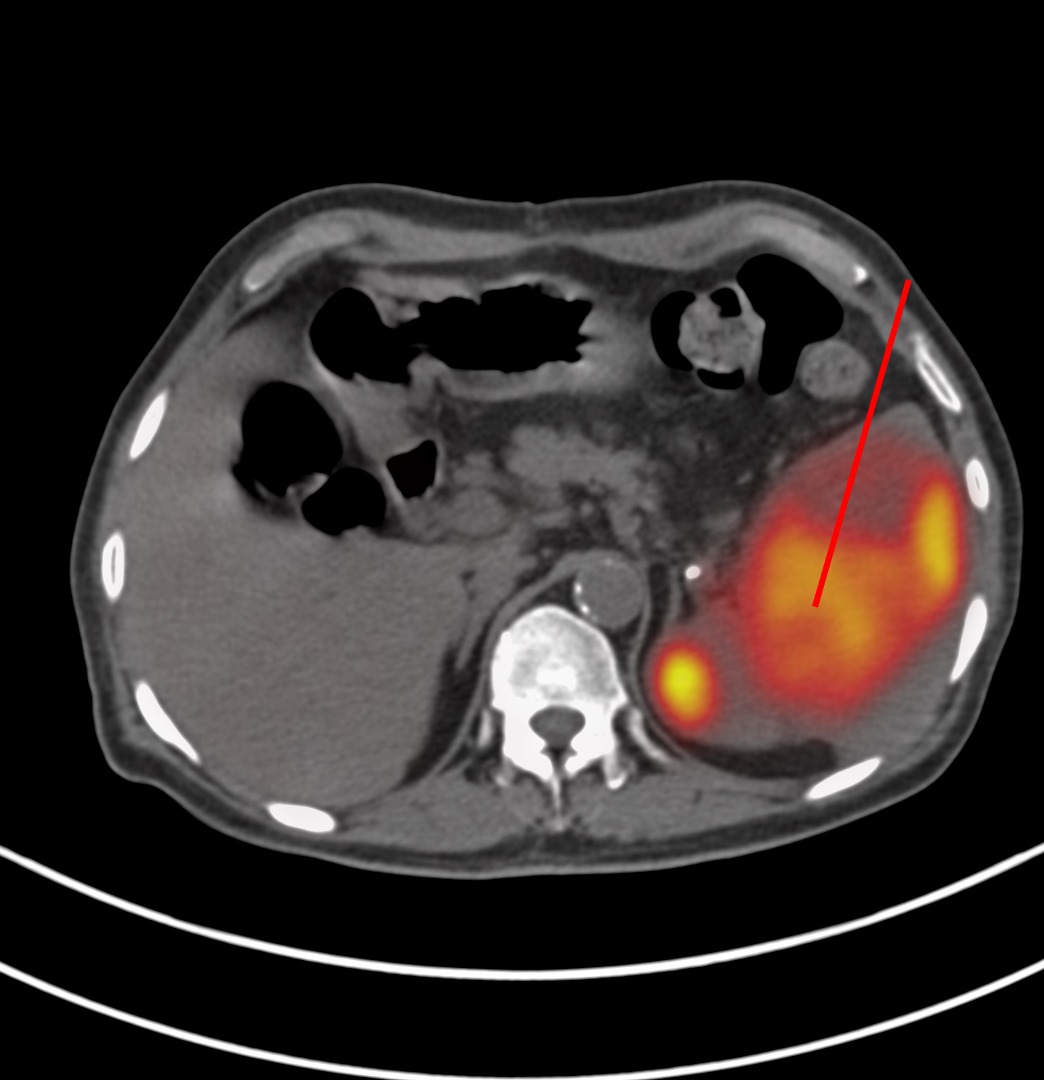

66-years old man presented with a mass in the spleen involving the tail of the pancreas.

The patient came for a biopsy and I decided to use an anterior approach in the supine position.

Findings: Large splenic mass involving tail of pancreas

Lesion Biopsied: Splenic mass

Position & Approach: Supine

Diagnosis: Non-Hodgkin’s lymphoma, large B-cell type